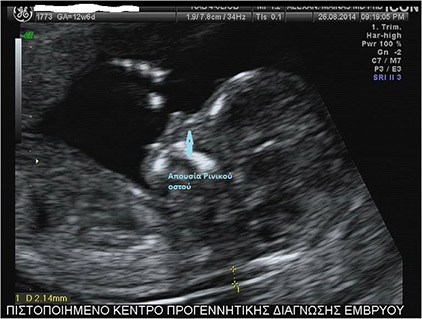

Son iki yılda, yukarıdaki kombinasyona, bilinen nazal kemik dışında, venöz sinüs akışında artan direnç ve fetüsün kalp triküspit kapak yetmezliği gibi yeni ultrasonografik göstergeler de eklenmiştir. Nazal kemiğin yokluğu veya venöz sinüsün patolojik akımı (a dalgası tersine dönmesi) ve kalbin triküspit kapak yetmezliğinin, 21-trizomili fetüslerde sırasıyla %60, %65 ve %55 oranlarında görülürken, normal fetüslerde bu oranlar sırasıyla %2,5, %3 ve %1'dir.